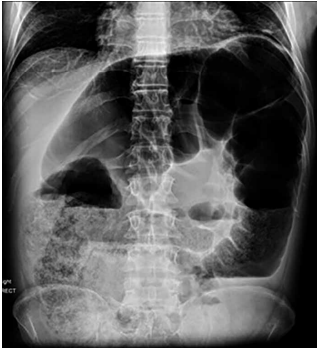

Homem, 76 anos de idade, apresenta dor abdominal, além de estar sem evacuar há 6 dias. Ao exame físico, nota-se dor à palpação e superficial difusa, além de descompressão brusca positiva. Realiza-se a radiografia de abdômen a seguir:

Enunciado 4892792-1

(Arquivo pessoal; imagem usada com autorização)

A hipótese diagnóstica é